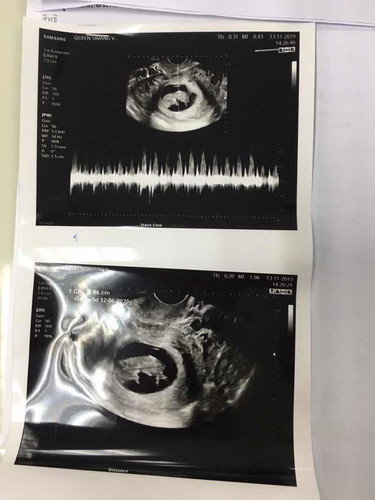

แท้งคุกคาม

มีใครดูใบซาวน์เป็นไหมคะ ดูให้หน่อยได้ไหมค่ะว่าเลือดมันออกรอบๆรกไหม คือเราเป็นแท้งคุกคาม ตอนนี้เลือดออกเยอะ ไม่แน่ใจว่าเลือดออกจากตรงไหน ถามหมอ หมอก็บอกแท้งคุกคามแค่นั้น